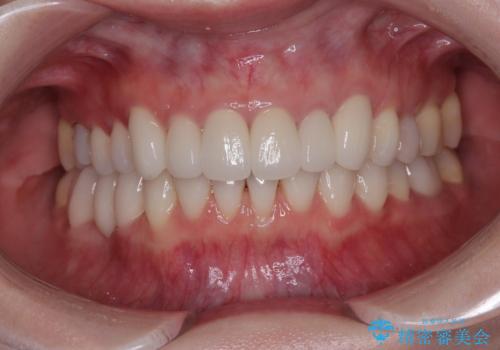

ほぼ歯根全てが露出 2度の歯肉移植術で自然な見た目に

1回目の処置で多少は被覆され歯肉が厚くなりましたが、十分とは言えなかったため、2回目の処置を行いました。

2回目の処置後には十分な厚みと、十分な被覆量を獲得することができました。